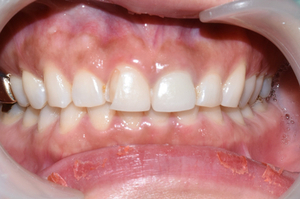

라미네이트는 본 뜬지 일주일 후에 완성이 되어 붙였으며

라미네이트 붙이고 일주일 후 촬영한 사진

치료 받은 4개의 앞니가 위와 같이 시원하고 하얗게 보이는 치아로 완성되었습니다.

모양 자체도 그 전의 마름모꼴의 치아보다 훨씬 개선이 된 것을 볼 수 있습니다.